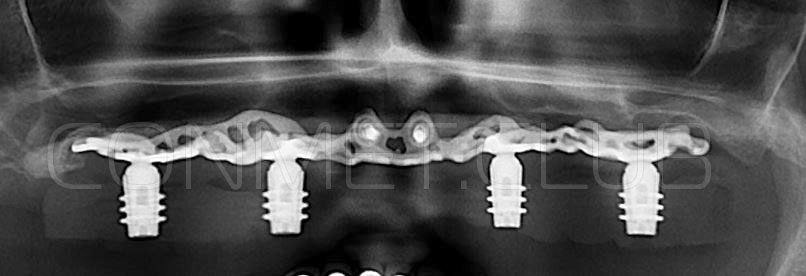

2. После этого произвели компьютерное моделирование самого имплантата и фиксирующих элементов. Примечательно, что в абатментах, использовался отлично зарекомендовавший себя и проверенный десятилетиями интерфейс КОНМЕТ! В результате получили несколько специальных файлов, позволяющих не только сделать сам имлантат, но еще до операции изготовить и сами зубы. Данные файлы передали в изготовление на специальном 3D оборудовании.

Имплантат напечатали из особого, биосовместимого, медицинского титана на предприятии имеющим соответствующую медицинскую лицензию. Толщина имплантата составила 0,8 мм, а вес всего несколько грамм!

Сама же операция длиться 20-50 минут в зависимости от количества утраченных зубов. В процессе этой операции, после проведенной местной анестезии, делается разрез на слизистой, она приподнимается и субпериостальный имплантат укладывается на кость. После этого рана фиксируется несколькими швами и все! Через 10-14 дней мягкие ткани срастаются и надкостница надежно удерживает имплантат на месте. Нет необходимости ждать несколько месяцев, как это бывает в случае с внутрикостными винтовыми имплантатами.

Новые, искусственные зубы фиксируются к этому имплантату стандартными, трансокклюзионными винтами на 1-14 день (в данном клиническом случае на 5 сутки) и по существу являются несъемными!